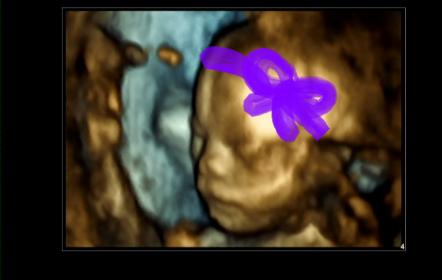

Attachment 7659 20 week princesss potty shot